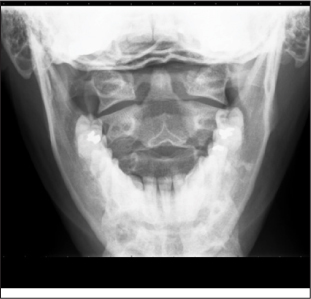

Odontoid View. The lateral margins of the C1 ring should be aligned within 1–2 mm of the articular masses of the axis. The articular masses of C2 should appear symmetrical, as should the joint spaces between the articular masses of C1 and C2, as long as there is no rotation of the head. The distance between the odontoid and the C1 medial border should be equal, but a discrepancy of 3 mm or more is often seen in patients without pathology. A vertical line bisecting the odontoid process should form a 90-degree angle with a line across the superior aspect of the C2 articular masses. (See Figure 3B.)

Figure 3B: Odontoid View